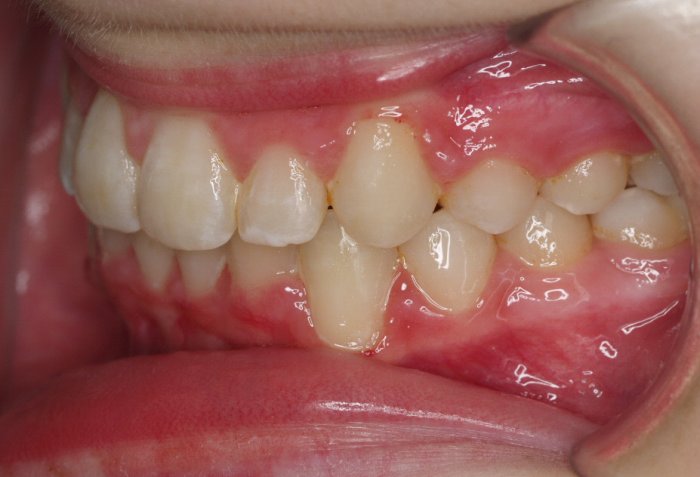

El paciente A.J. de 11 años, acude a nuestra consulta con apiñamiento maxilar importante. El canino lateral (12) está en mordida cruzada. Presenta una Clase II molar y canina, y la línea media está desviada. Se realizó un tratamiento con brackets autoligables metálicos de smartclip 022. La duración del tratamiento fue de 22 meses.

El paciente actualmente ha terminado el tratamiento con brackets y lleva una contención fija de 2-2 en maxilar y 3-3 en mandibular; para complementar también lleva una férula ESSIX durante la noche.